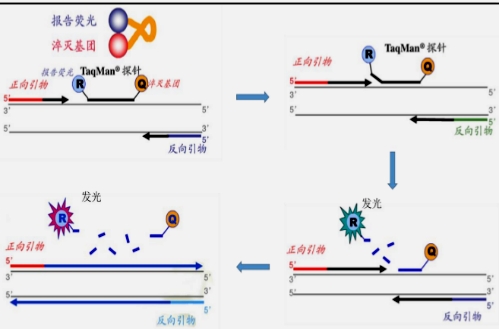

3.随着分子病理学检测技术的发展,其在结核病的诊断中占据着越发重要的地位。由于其快捷、高敏感性和特异性强等特征,可有效提高病理标本中MTB检出率,对结核病的诊断及鉴别诊断具有重要意义,常用实时荧光定量PCR、高分辨熔解曲线技术等分子技术协助结核病的诊断。

病理石蜡组织切片形态学查见肉芽肿病变、坏死等,就是病理形态学考虑结核病时,一般需要石蜡组织再切片加做结核分子检测(TB-PCR)协助诊断,若分子病理检测阳性是诊断结核病的有力证据。